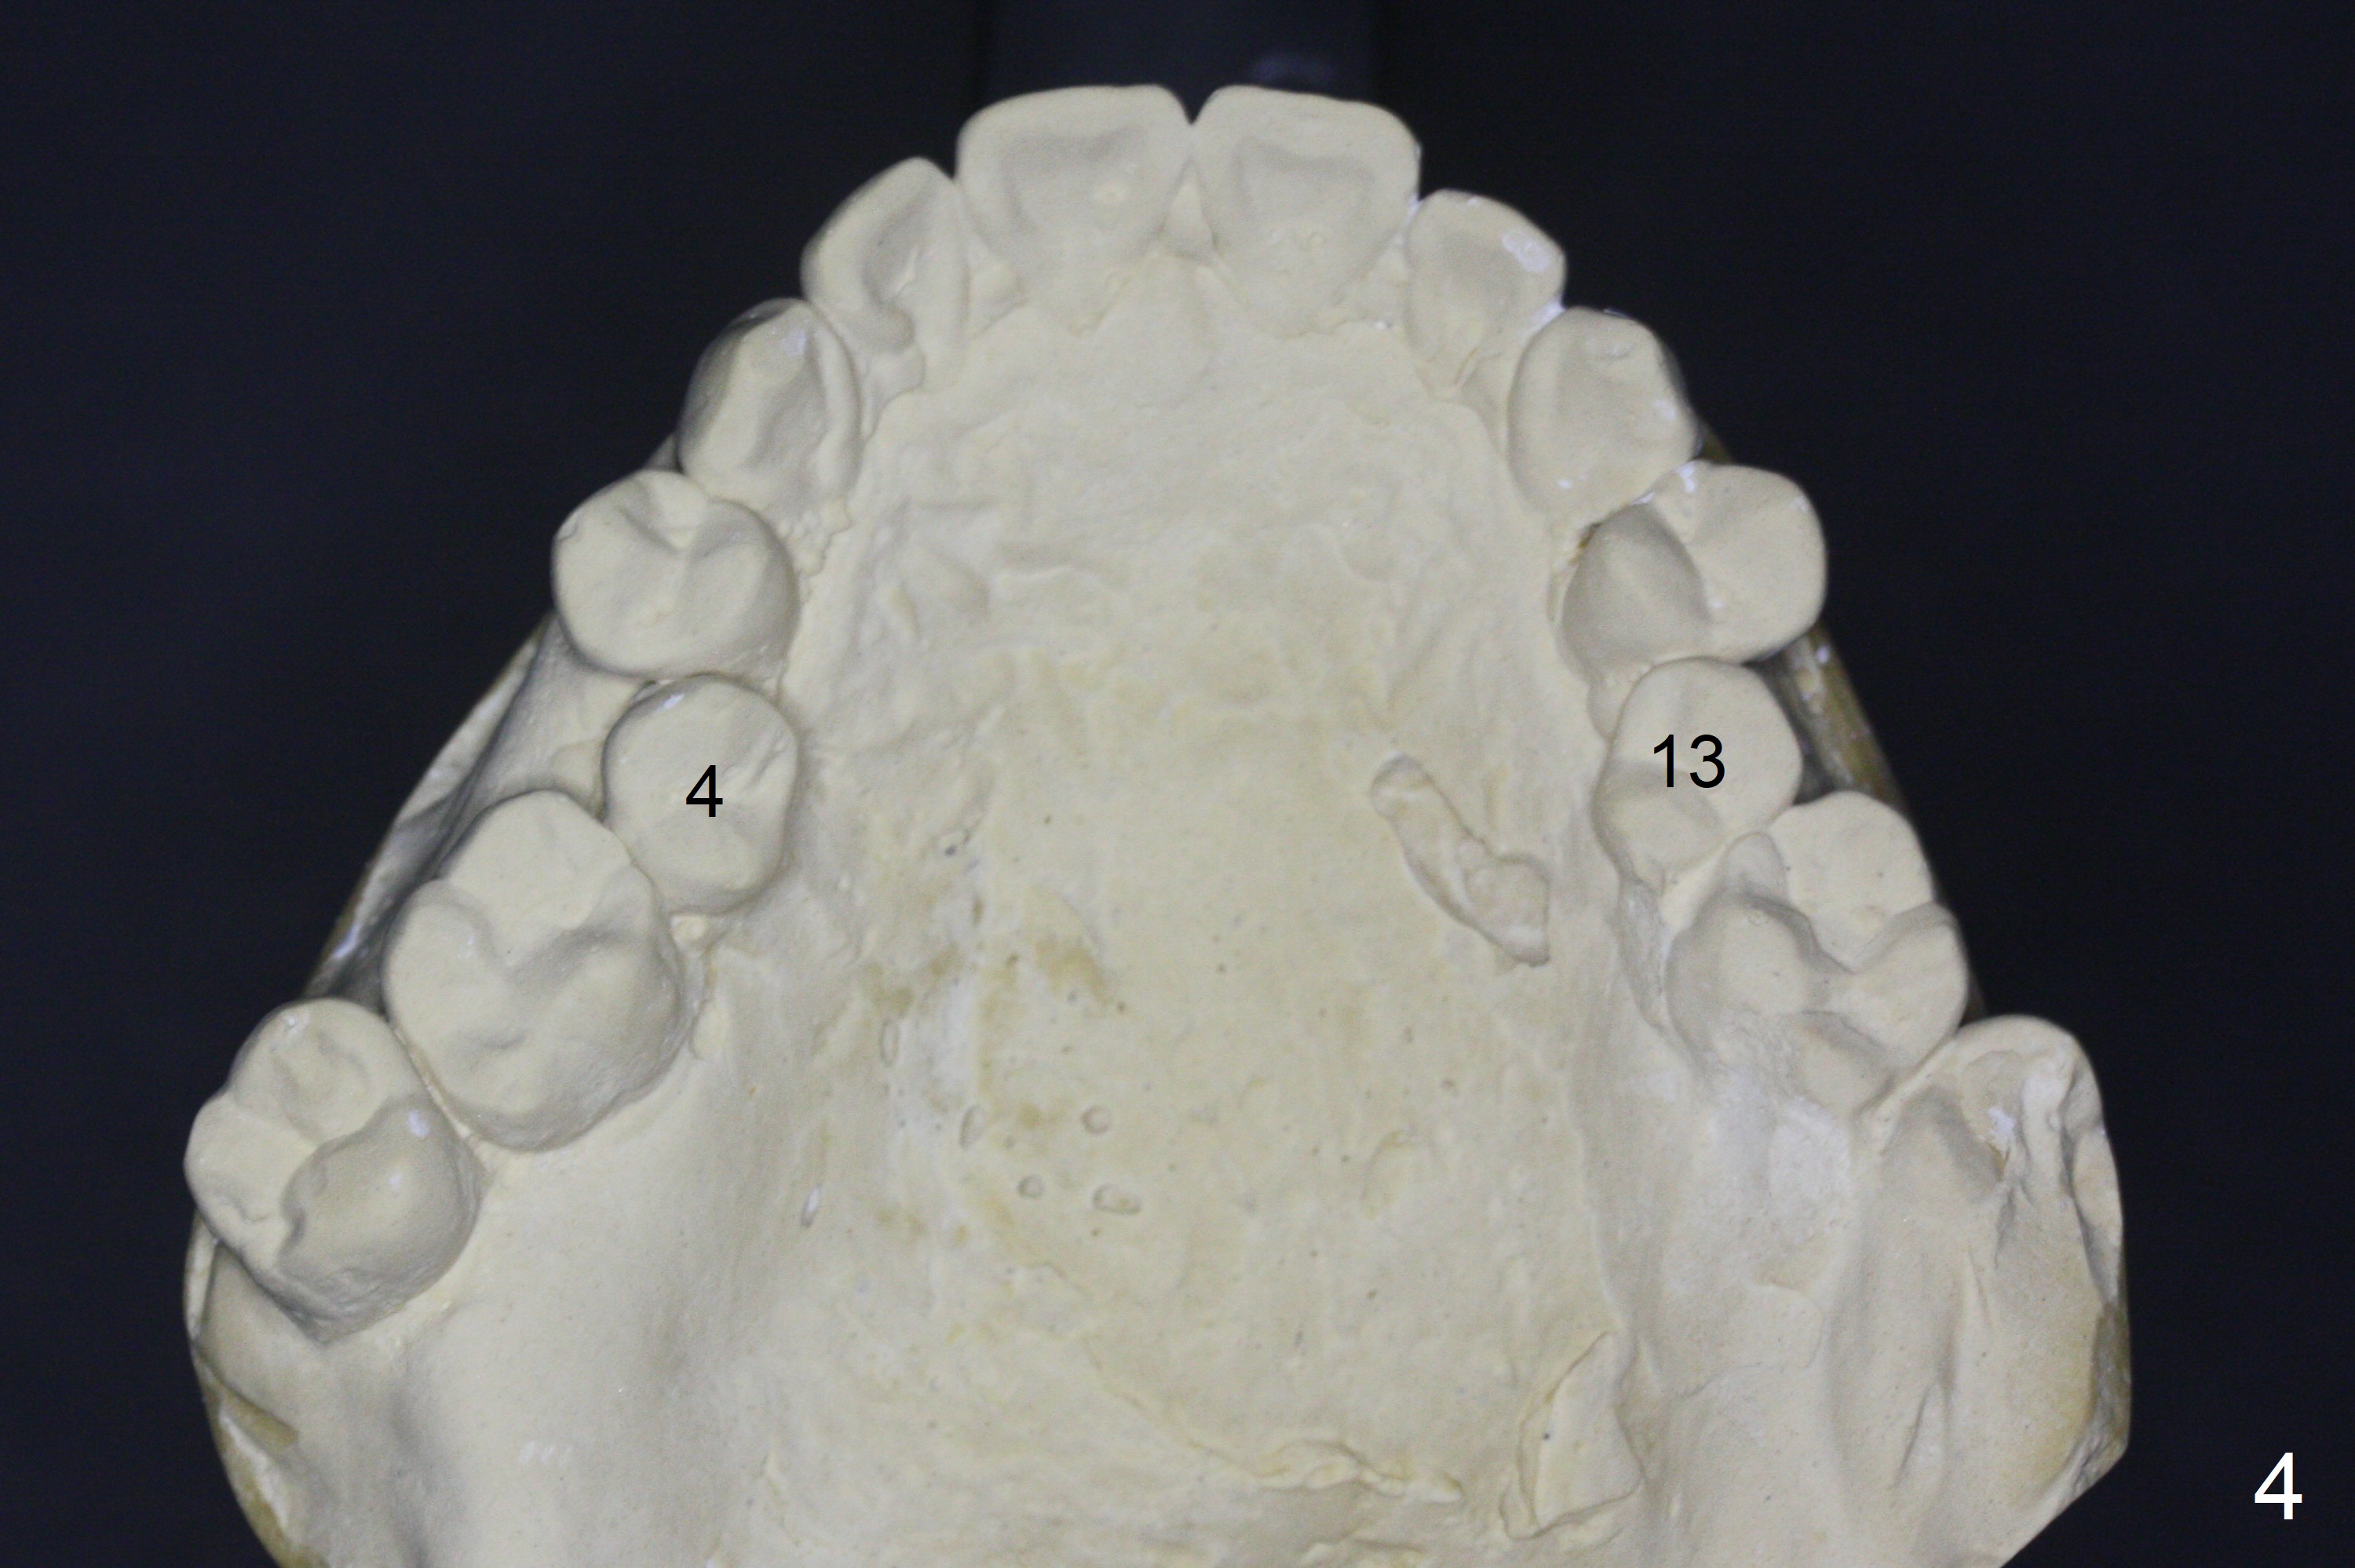

A 64-year-old man has discomfort with the lower left bridge and a loose tooth on the left (Fig.1). It appears that 4 implants are to be placed at #18,19,30 and 31. Since the tooth #4 and 13 are palatalized (Fig.2-4), the teeth #2 and 3 are mesialized (Fig.2 arrow). Besides, the ridge at #30 must be atrophic due to long termed edentulism. A small-diameter implant will be placed at #30 with premolar width (Fig.6-13), while the implant at #31 will be placed distal (arrow, as compared to Fig.2). To establish harmonious occlusion at provisional and final stages, the palatal slope of the mesiopalatal cusp of the tooth #2 will be adjusted (Fig.10).